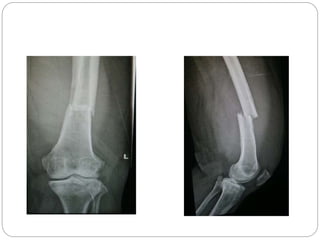

This document discusses 8 oncology cases. Case 1 involves a 40-year old female with right knee pain. Case 2 is a 28-year old male with a left subtrochantric fracture from a MVA who is now experiencing increasing left knee pain and swelling. Biopsy results showed high-grade osteosarcoma. Case 3 is a 30-year old female with breast cancer and bone metastases causing bilateral hip pain.